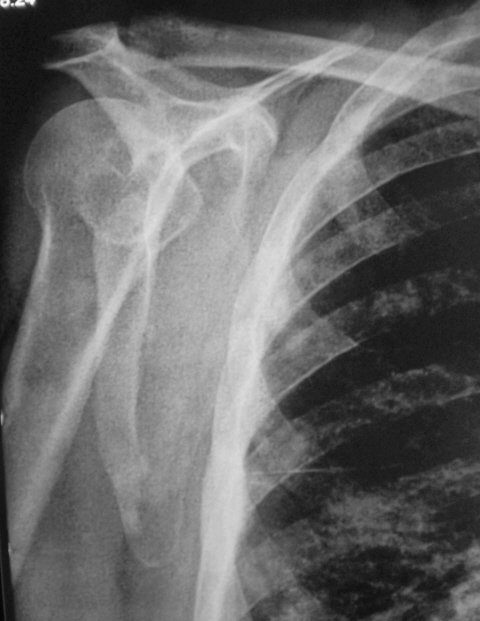

Иллюстрации 1, 2. На обзорной рентгенограмме органов грудной полости, произведенной в прямой стандартной проекции с обеих сторон, на фоне усиленного и обогащенного легочного рисунка определяются множественные полиморфные очаговые тени различных размеров, преимущественно средней интенсивности во всех отделах легочных полей. Тень корней преимущественно левого представляется несколько расширенной, гомогенизированной. Справа в малой междолевой щели плевра утолщена.